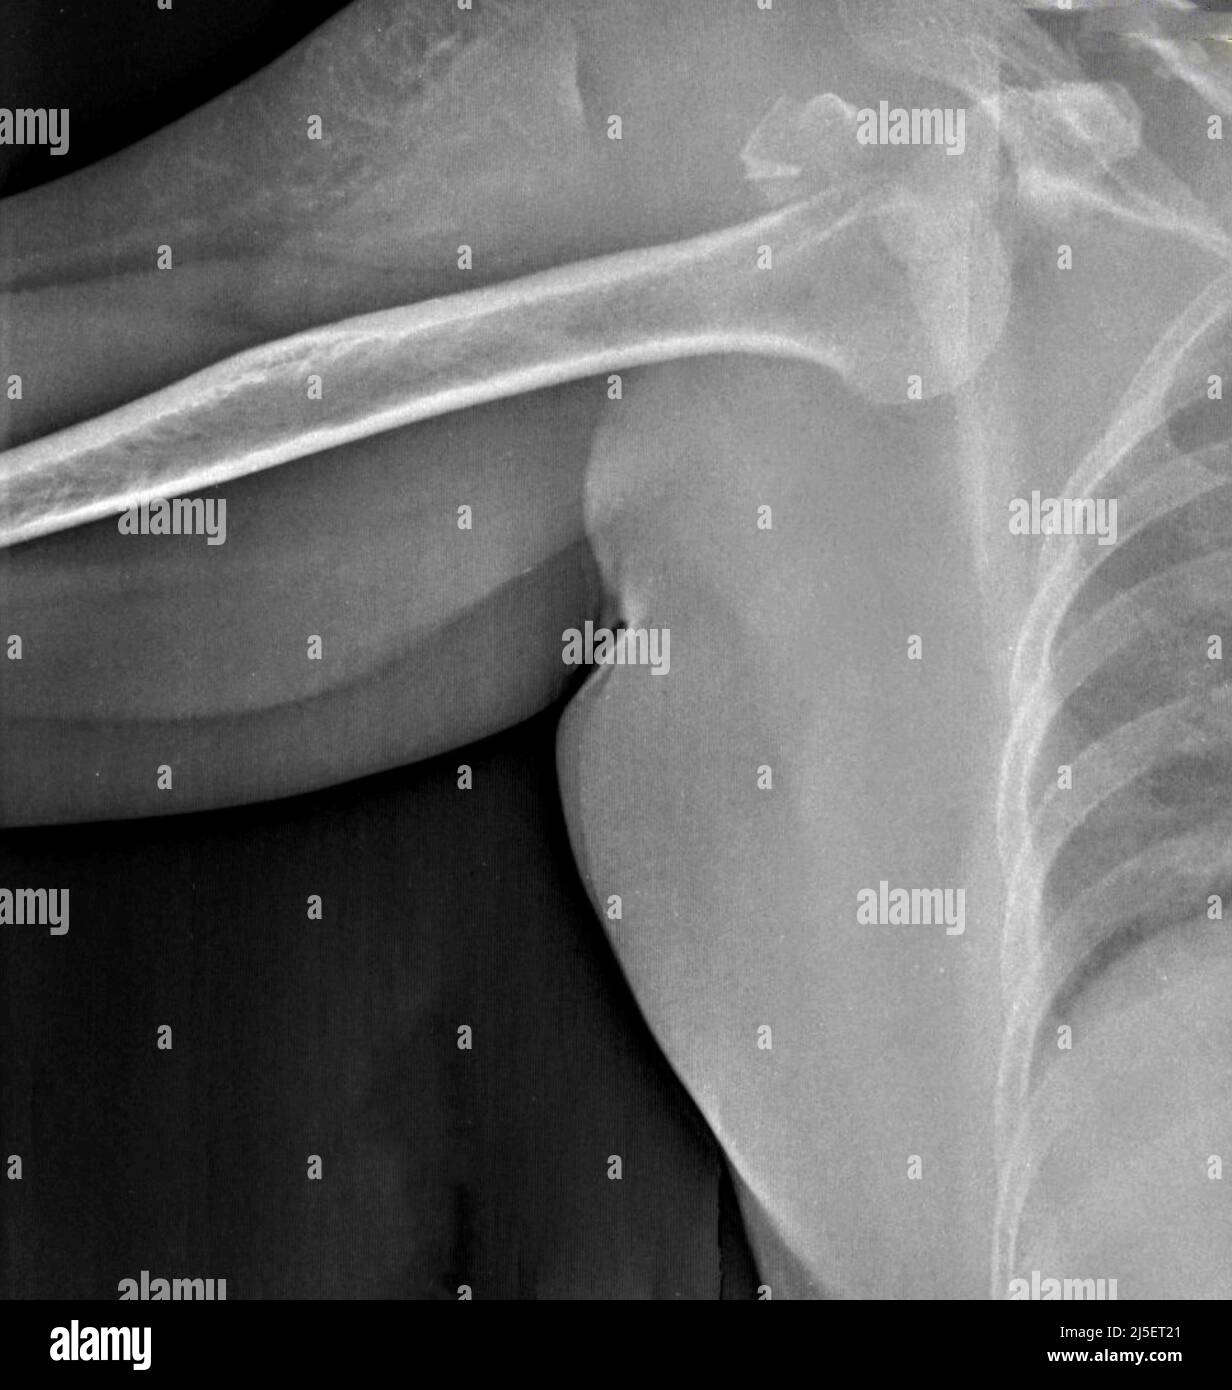

X Ray Of Dislocated Right Shoulder . Often, it is important to evaluate the ligaments, and a magnetic resonance imaging (mri) scan is helpful in doing so. Shoulder dislocation is a term often used loosely to indicate dislocation of the head of the humerus from the glenoid of. most shoulder dislocations (>95%) occur in the anterior direction and are usually the result of trauma. 1 2 3 optimal management can prevent recurrent. Choosing a search strategy and utilising it consistently is a helpful method to overcome common errors seen in diagnostic. The humeral head will lie medial and inferior to. For specific dislocation types please refer to the following articles: this article contains a general discussion on shoulder dislocation. If it is dislocated, a doctor will rotate your arm back into place.

FileDislocated shoulder Xray 03.png

Dislocated shoulder x ray hires stock photography and images Alamy X Ray Of Dislocated Right Shoulder The humeral head will lie medial and inferior to. Shoulder dislocation is a term often used loosely to indicate dislocation of the head of the humerus from the glenoid of. this article contains a general discussion on shoulder dislocation. For specific dislocation types please refer to the following articles: If it is dislocated, a doctor will rotate your arm. X Ray Of Dislocated Right Shoulder.